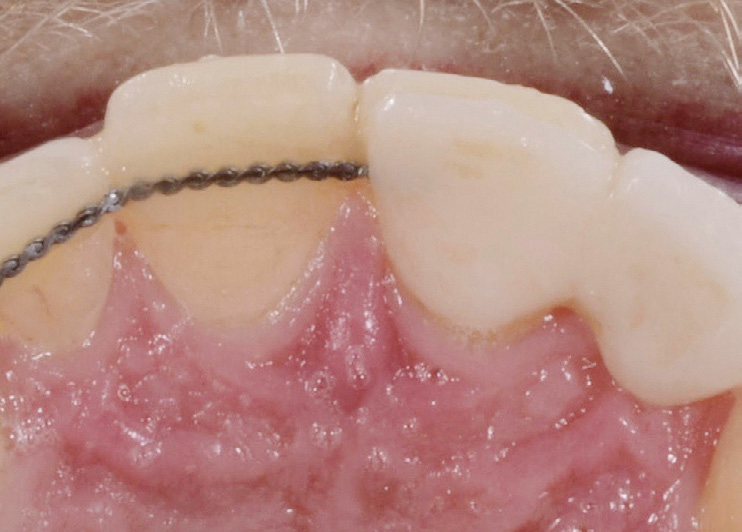

Maryland bridge with retention element. Pre-treatment of bonding surface was done by sandblasting followed by priming.